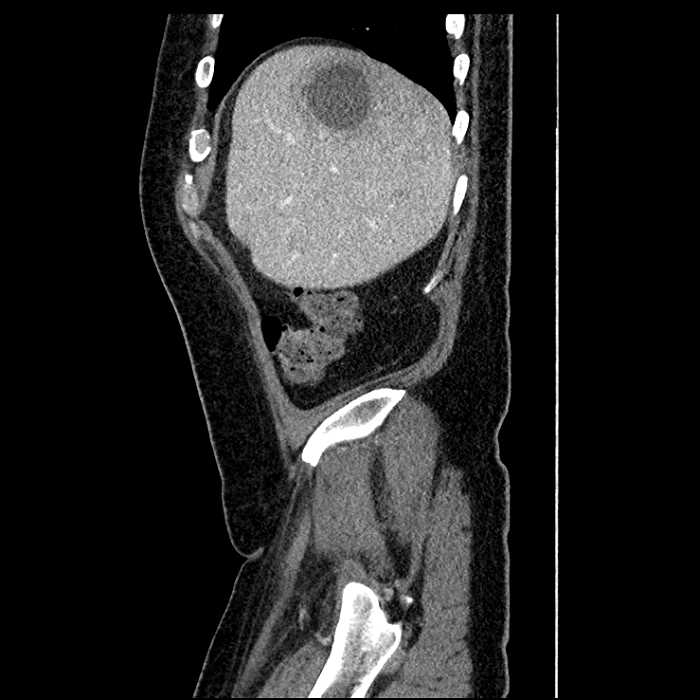

• Large fluid density structure in hepatic segments 7 and 8 measuring 10 x 7 x 7 cm with internal septation and circumferential ill-defined low density compatible with edema

• Clearly marginated fluid density structure in segment 7 and several other scattered tiny hypodensities, which likely represent cysts

• Hepatic abscess

Acute sigmoid diverticulitis complicated by a small contained perforation and a large abscess in the right hepatic lobe. Additional small subcapsular abscesses along the anterior margin of the left hepatic lobe.

• The classic CT imaging appearance is a double target sign with internal low density surrounded by an internal enhancing rim (capsule) and a low density external rim (edema)

• Abscesses may be unilocular or multilocular

• Gas is present in a minority of cases

• Unfortunately, necrotic tumors can have an overlapping imaging appearance, so it is important to follow these to resolution

Hepatic abscess showing the double target sign with low density internally surrounded by a thin inner enhancing rim (red arrow) and ill-defined outer low density rim (yellow arrow). Blue arrow indicates an internal septation. Red arrows: additional smaller subcapsular abscesses. Red arrow: focal contained perforation associated with diverticulitis.